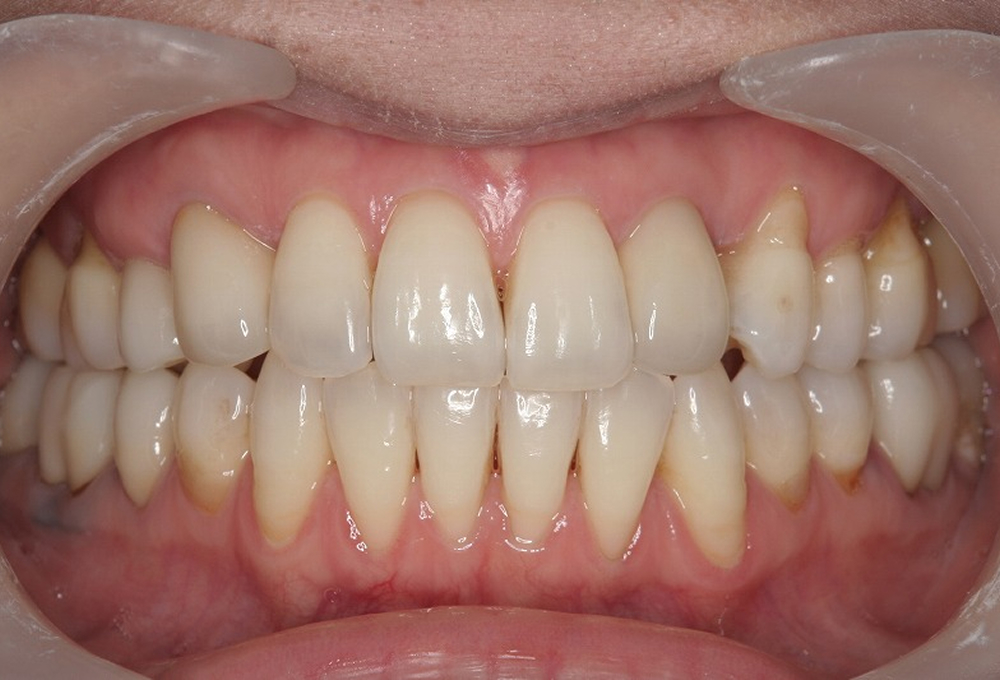

①術前 開咬